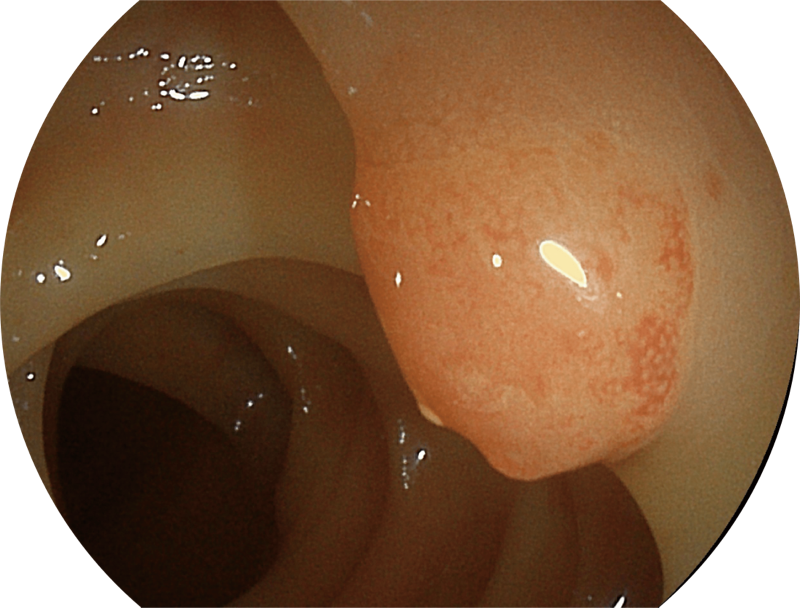

能够凸显黏膜浅层和中层血管轮廓,适用于中、远景观察下的病灶识别和早癌筛查。

白光图像

SFI图像